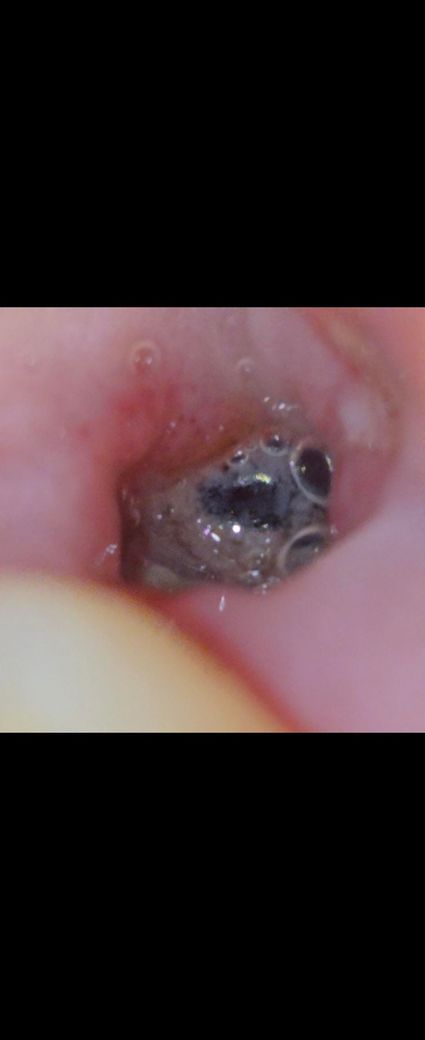

사랑니 발치4일째인데 이거 드라이소켓인가요ㅠㅠ? 사진있어요 혐오주의ㅜㅜ

저번주 금요일(8/2) 아래 왼쪽 사랑니 올곧게 나있어서 그냥 뺀찌? 같은걸로 바로 뽑고 실로 봉합 안해줬어요ㅠㅠ 피딱지같은게 앉은적이 없구 계속 구멍 나있는 상태인데..ㅠㅠ 아직도 통증이 있어요ㅠㅠ 그리고 아래 앞니쪽도 시리고? 욱신거리는? 통증이 생겼어요ㅠㅠ 드라이소켓인가 그거인가요..ㅜㅜ

그리고 저 검은부분은 심장따라서 울룩울룩 움직여요ㅠㅠㅠ

침인지뭔지고여있어요ㅠㅠ

발치한 부위에 보이는 검은색은 드라이소켓이 아닌 혈병일 가능성이 있습니다. 발치한 부위는 발췌한 부위가 아무는데 2주 정도의 시간이 걸리기 때문에 그 이전까지는 해당 부위가 자극되지 않도록 하는 것이 좋습니다

사진상으로 드라이소켓은 아닌 것으로 보이며, 해당부위가 잘 아물고 있는 것으로 보입니다. 염증이 덧나지 않도록 소독용 가글액을 사용하는 것을 권합니다.